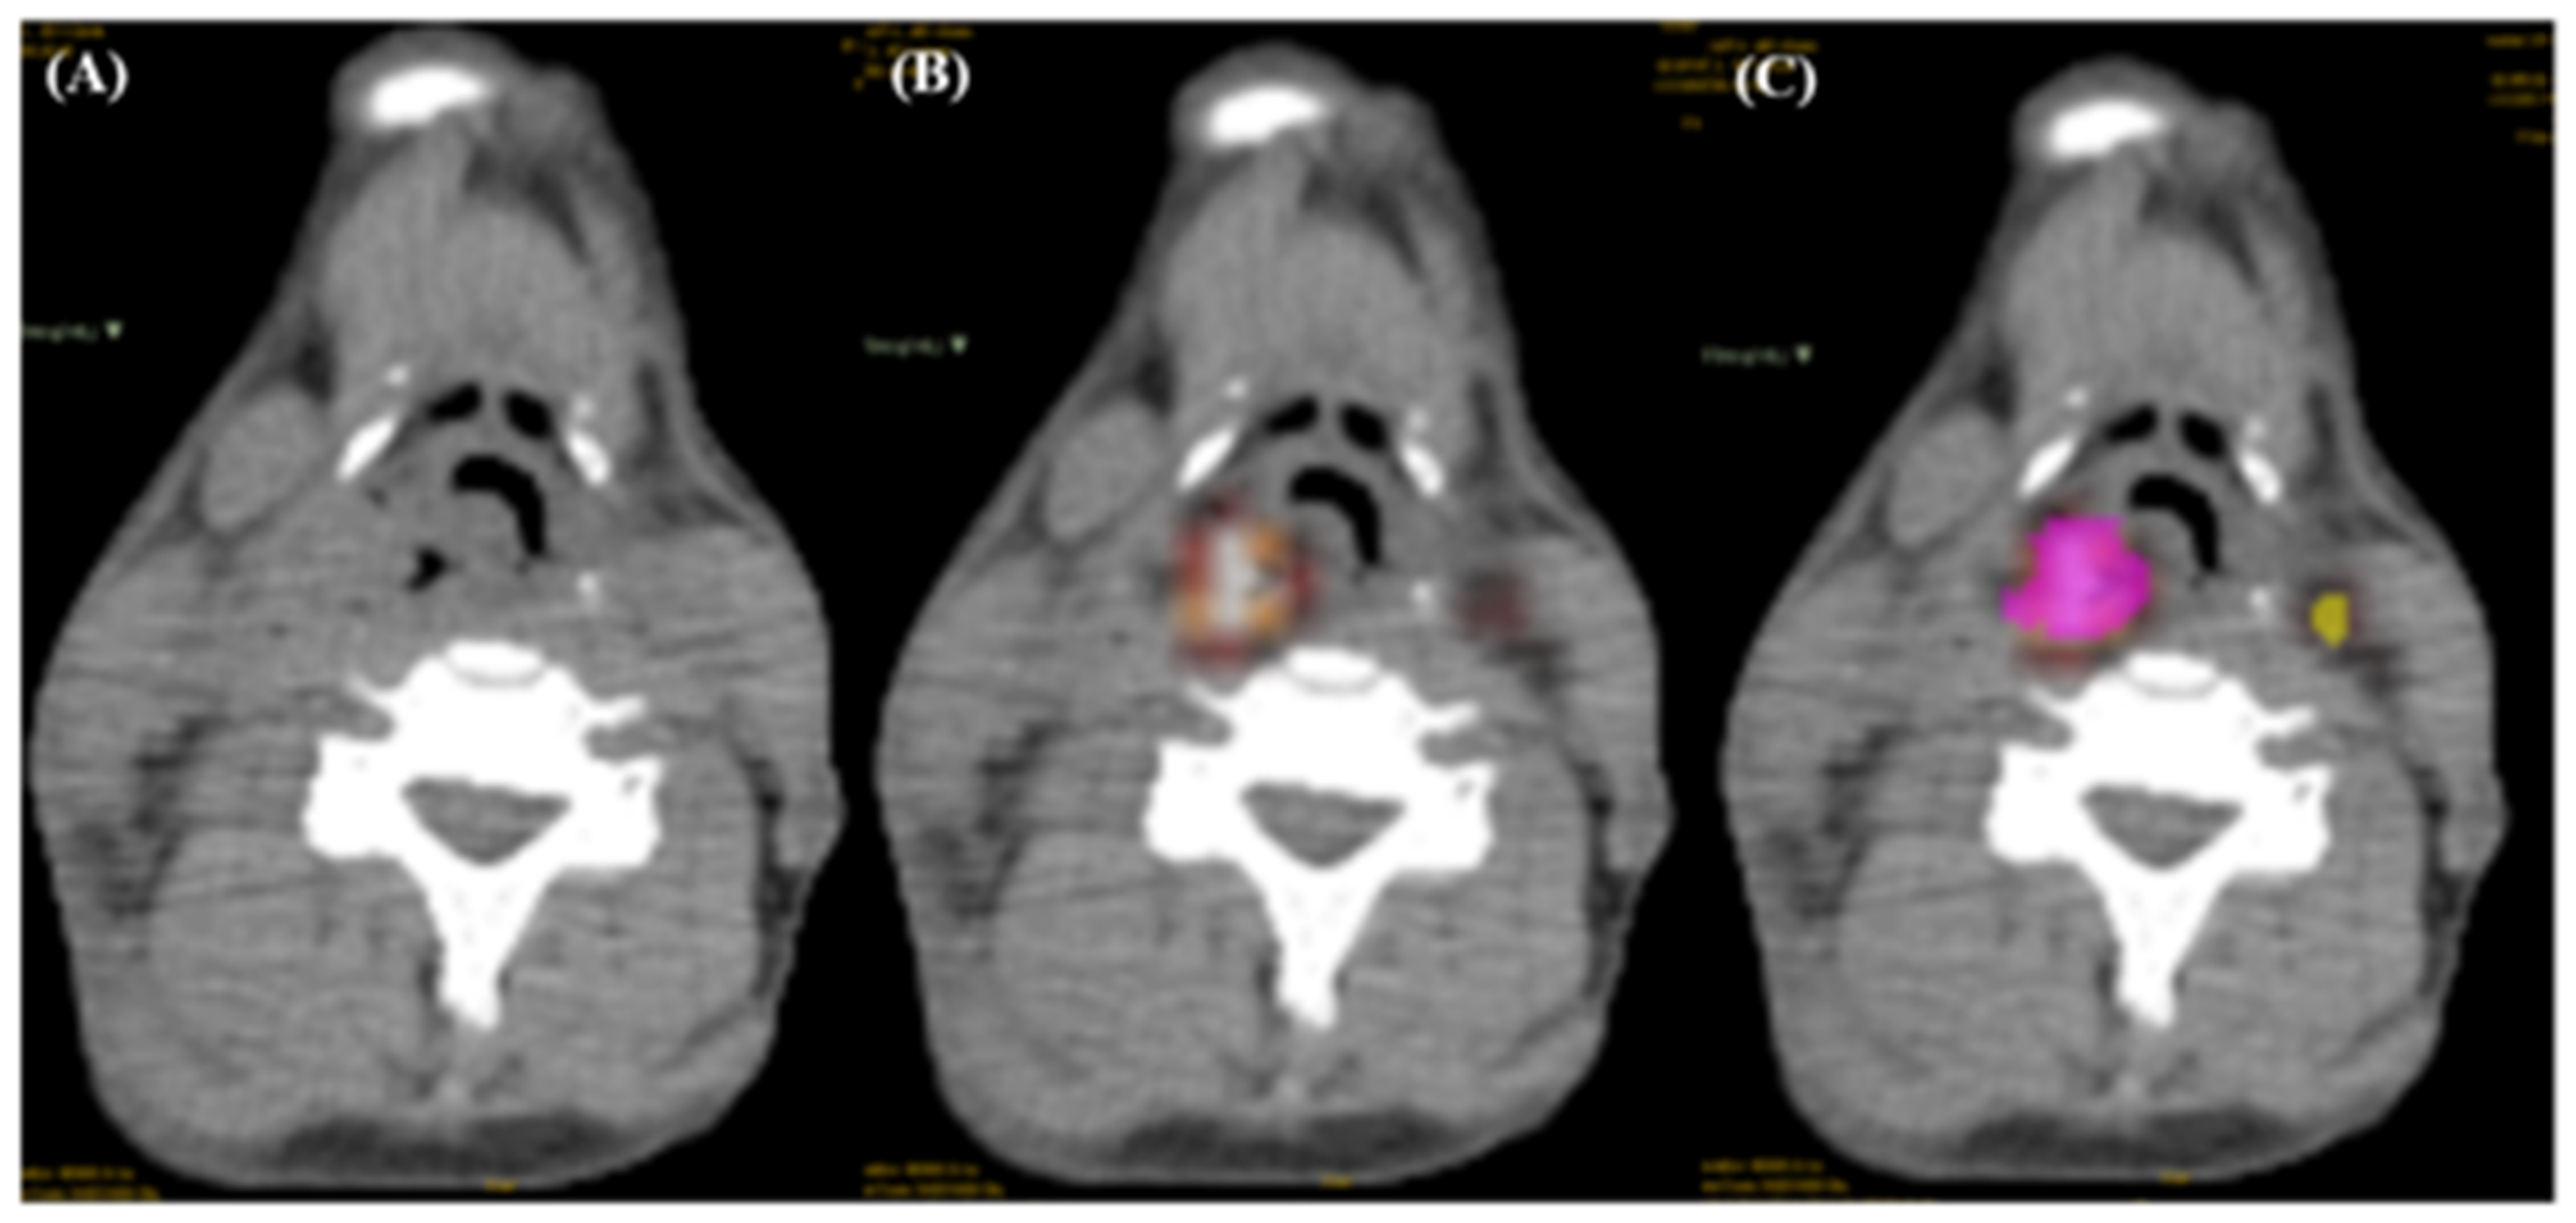

2.3. Tumor Region Delineation